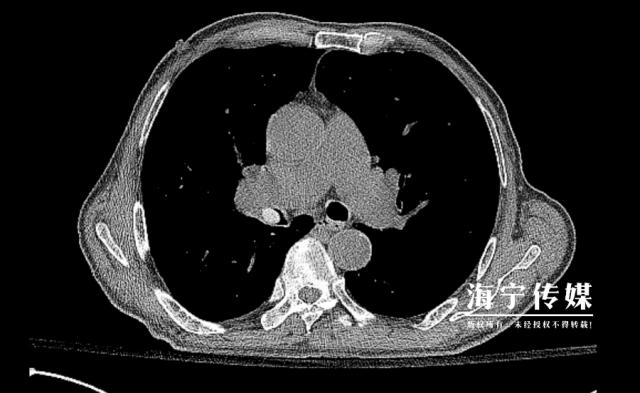

另一例 83 老年妇女病人的病情更加危险,由于帕金森病导致吞咽功能下降,她误吸枇杷核后突发心肺骤停。抢救后发现果核嵌入气道,最后通过高难度气管镜取出。柳志浩指出:“一旦气道误吸入异物,这类基础疾病患者的死亡率可以达到普通人群。 3 倍以上。"

据医生介绍,枇杷核表面光滑的特点给治疗带来了特殊挑战。常规的异物钳很难夹住,所以需要用圈套器配合网袋技术,在全身麻醉下进行精细操作。